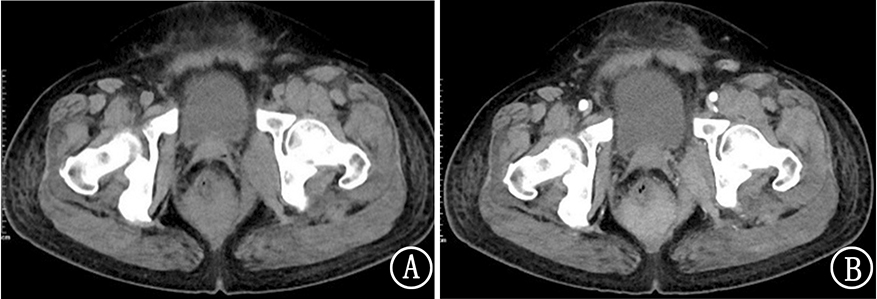

孙淑琴, 钱秋红, 张友忠.盆腔原发弥漫性大B细胞淋巴瘤1例[J]. 国际肿瘤学杂志, 2022, 49(5): 319-320. |